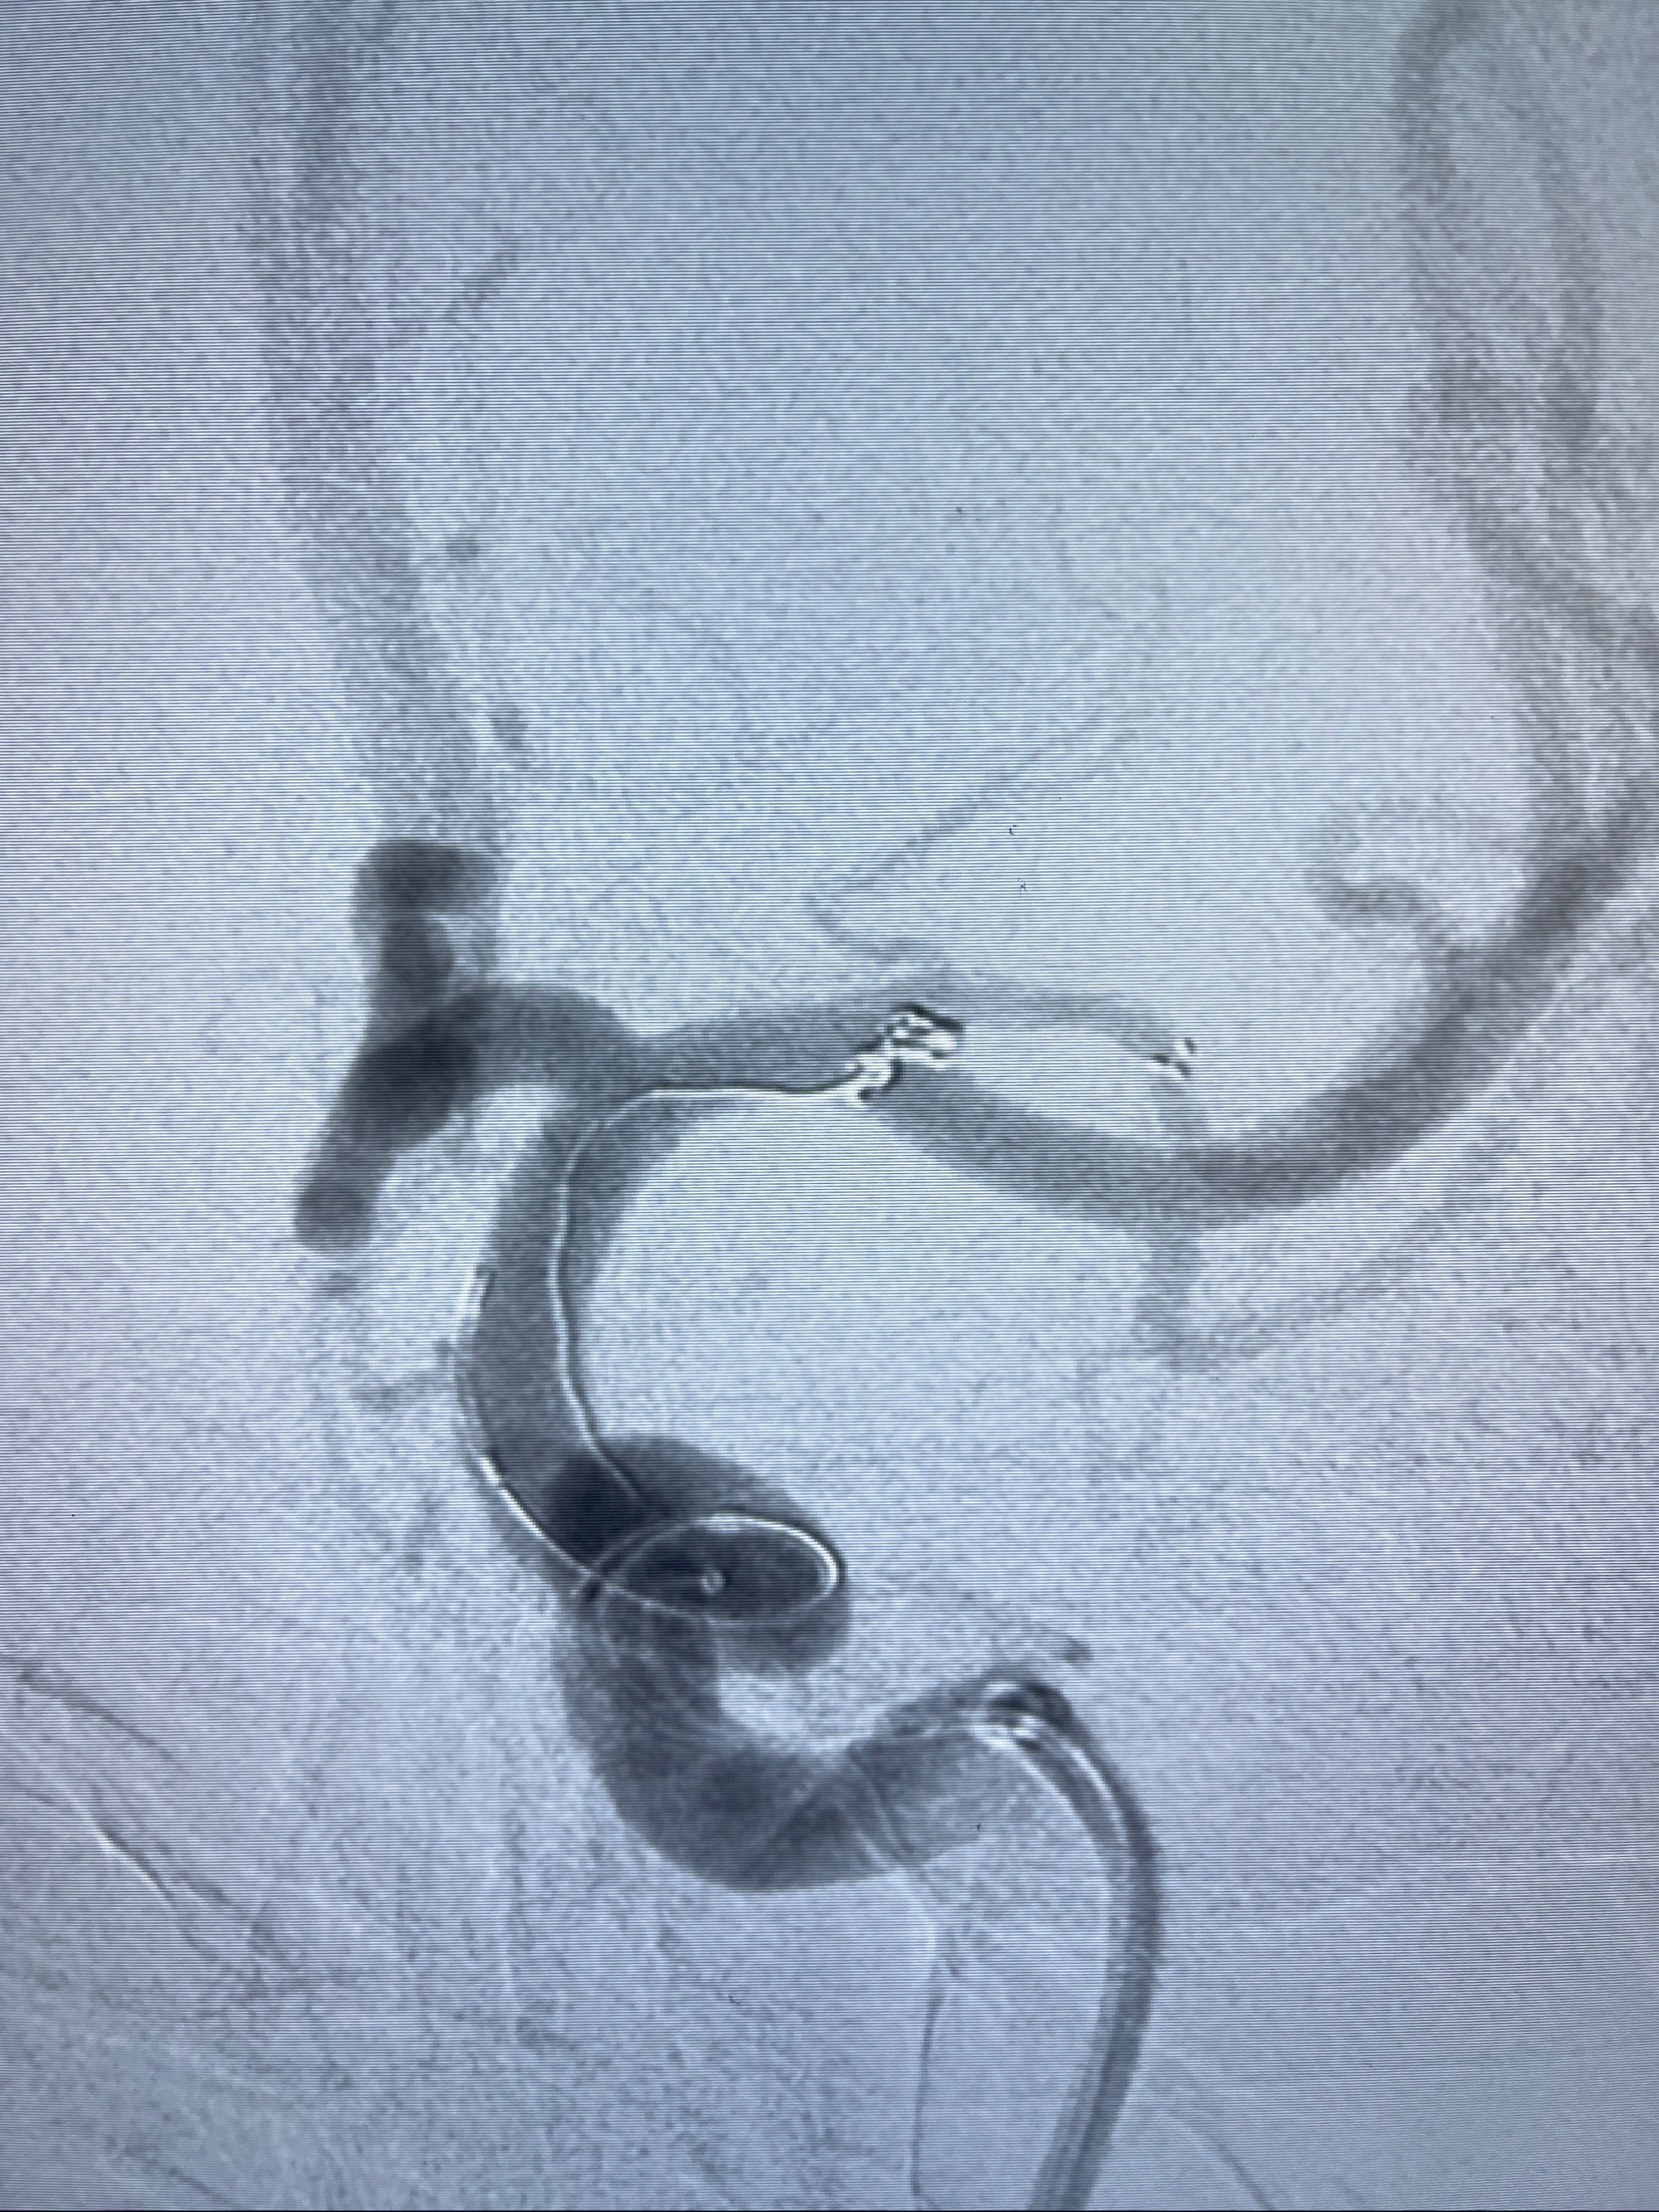

2023-08-14DSA:

左侧大脑中动脉动脉瘤,约2.6-2.8-3.4-2mm大小(瘤颈部、瘤体部、瘤高)

1.左侧大脑中动脉动脉瘤,约2.6-2.8-3.4-2mm大小(瘤颈部、瘤体部、瘤高)

2.外科手术夹闭or介入支架辅助栓塞

麻醉苏醒佳,遵嘱动作

术后即刻CT